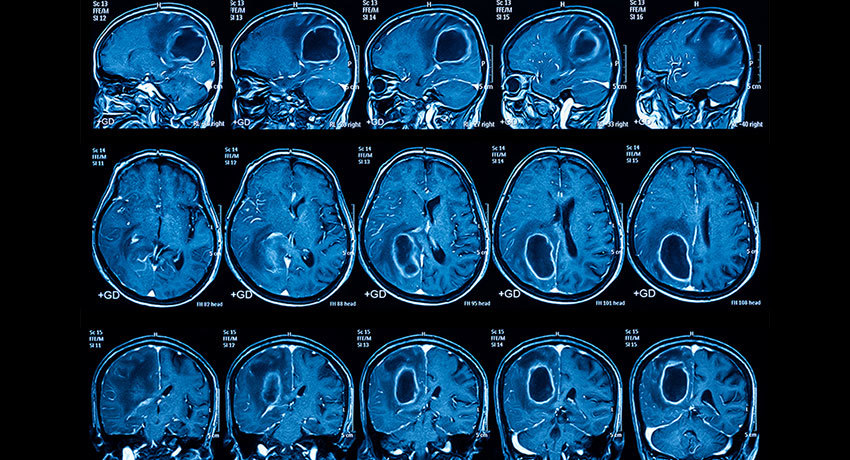

МРТ головного мозга

Магнитно-резонансная томография головного мозга — высокоинформативное исследование, которое позволяет детально изучить ткань головного мозга, кровеносные сосуды и другие внутричерепные структуры, диагностировать многие заболевания.

Во время этой процедуры применяется сильное магнитное поле, с помощью которого получают снимки с послойными срезами головы и трехмерные изображения. В некоторых случаях для лучшей визуализации проводится контрастирование. МРТ головного мозга и шейного отдела позвоночника широко применяется в неврологии, нейрохирургии, при подозрении на опухоли и сосудистые патологии.

МРТ артерий головного мозга проводят с контрастированием. Внутривенно вводят специальный препарат, который «прокрасит» кровеносные сосуды и позволит получить их четкие контуры на снимках.

Если проводится МРТ головного мозга без контраста, вас сразу попросят пройти в кабинет и лечь внутрь аппарата. Если требуется контрастирование, предварительно вам введут внутривенно препарат гадолиния.

Во время исследования нужно лежать неподвижно, чтобы изображения получились четкими. Диагностический стол перемещается, в это время аппарат делает серию снимков. Врач находится в соседнем помещении и общается с пациентом через микрофон.